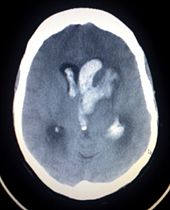

Hemorrhagic stroke

Intracranial hemorrhage is the accumulation of blood anywhere within the skull vault. A distinction is made between intra-axial hemorrhage (blood inside the brain) and extra-axial hemorrhage (blood inside the skull but outside the brain). Intra-axial hemorrhage is due to intraparenchymal hemorrhage or intraventricular hemorrhage (blood in the ventricular system). The main types of extra-axial hemorrhage are epidural hematoma (bleeding between the dura mater and the skull), subdural hematoma (in the subdural space) and subarachnoid hemorrhage (between the arachnoid mater and pia mater). Most of the hemorrhagic stroke syndromes have specific symptoms (e.g. headache, previous head injury).

Intracerebral hemorrhage (ICH) is bleeding directly into the brain tissue, forming a gradually enlarging hematoma (pooling of blood). It generally occurs in small arteries or arterioles and is commonly due to hypertension, trauma, bleeding disorders, amyloid angiopathy, illicit drug use (e.g. amphetamines or cocaine), and vascular malformations. The hematoma enlarges until pressure from surrounding tissue limits its growth, or until it decompresses by emptying into the ventricular system, CSF or the pial surface. A third of intracerebral bleed is into the brain's ventricles. ICH has a mortality rate of 44 percent after 30 days, higher than ischemic stroke or even the very deadly subarachnoid hemorrhage.

Stroke is diagnosed through several techniques: a neurological examination, CT scans (most often without contrast enhancements) or MRI scans, Doppler ultrasound, and arteriography. The diagnosis of stroke itself is clinical, with assistance from the imaging techniques. Imaging techniques also assist in determining the subtypes and cause of stroke. There is yet no commonly used blood test for the stroke diagnosis itself, though blood tests may be of help in finding out the likely cause of stroke.

Imaging

For diagnosing hemorrhagic stroke in the emergency setting:

- CT scans (without contrast enhancements)

- sensitivity= 89%

- specificity= 100%